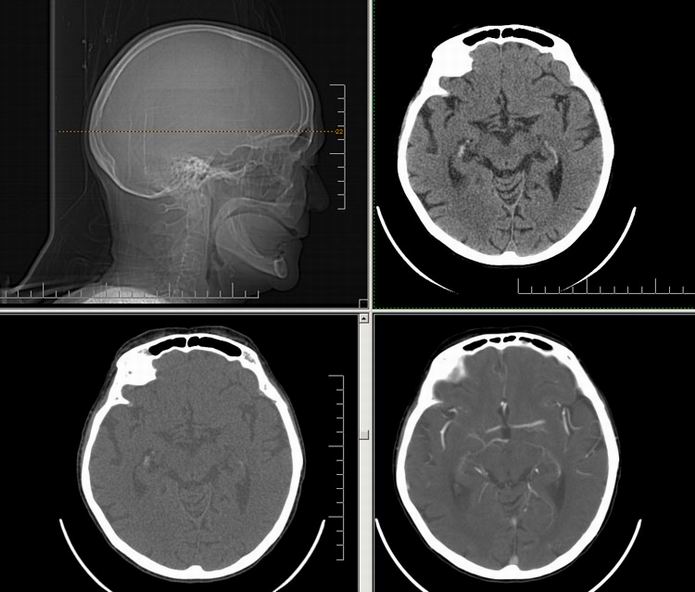

Est ce que qqun a des coupes axiales de crâne pour m'aider à réviser mon anatomie. Merci

Pour compléter tes révisions, Poupette vient de nous faire parvenir ces planches bien utiles: Planches de coupes axiales cérébrales, dans la rubrique COURS / ANATOMIE